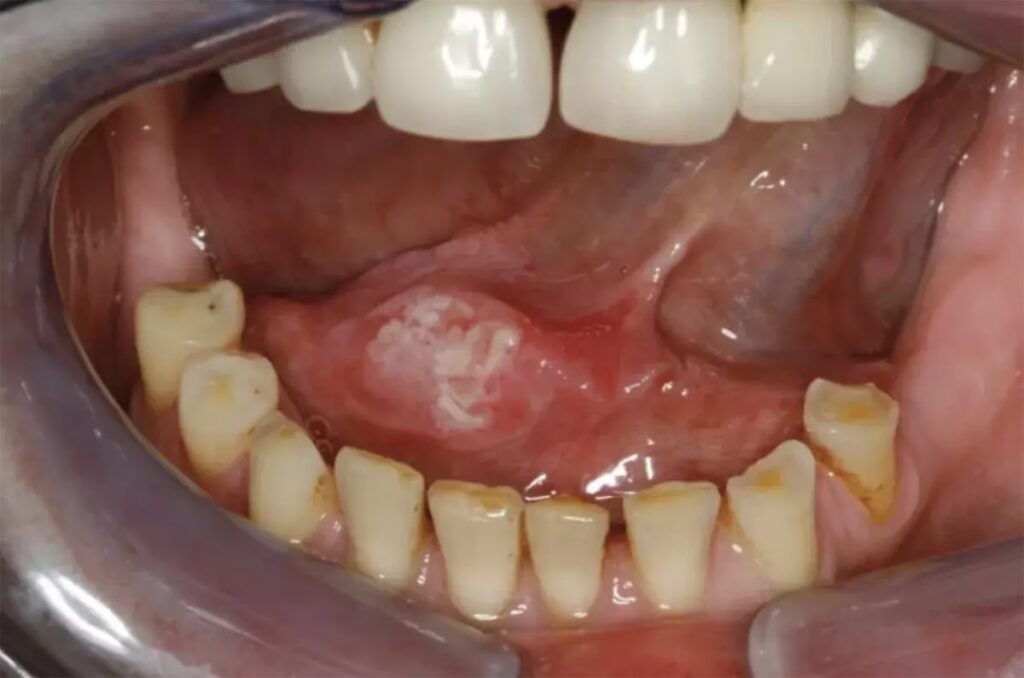

- Røde (erytroplaki) eller hvide (leukoplaki) pletter på tungen, som ikke kan skrabes af.

De tidligste tegn kan omfatte smerter i munden og en knude eller et sår på siden af tungen, der kan være smertefuldt, ikke heler og bløder let. Røde eller hvide pletter, der ikke forsvinder, er også et tidligt advarselstegn.